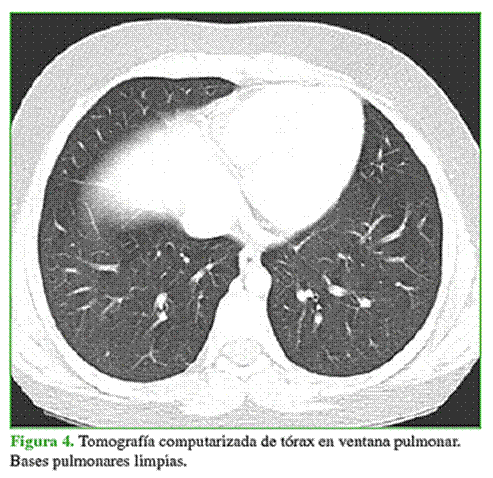

La paciente es sometida a estudios para establecer el estadio de la lesión. La tomografía computarizada de tórax no muestra lesiones a distancia (Figura 4). El centellograma óseo es normal (Figura 5).